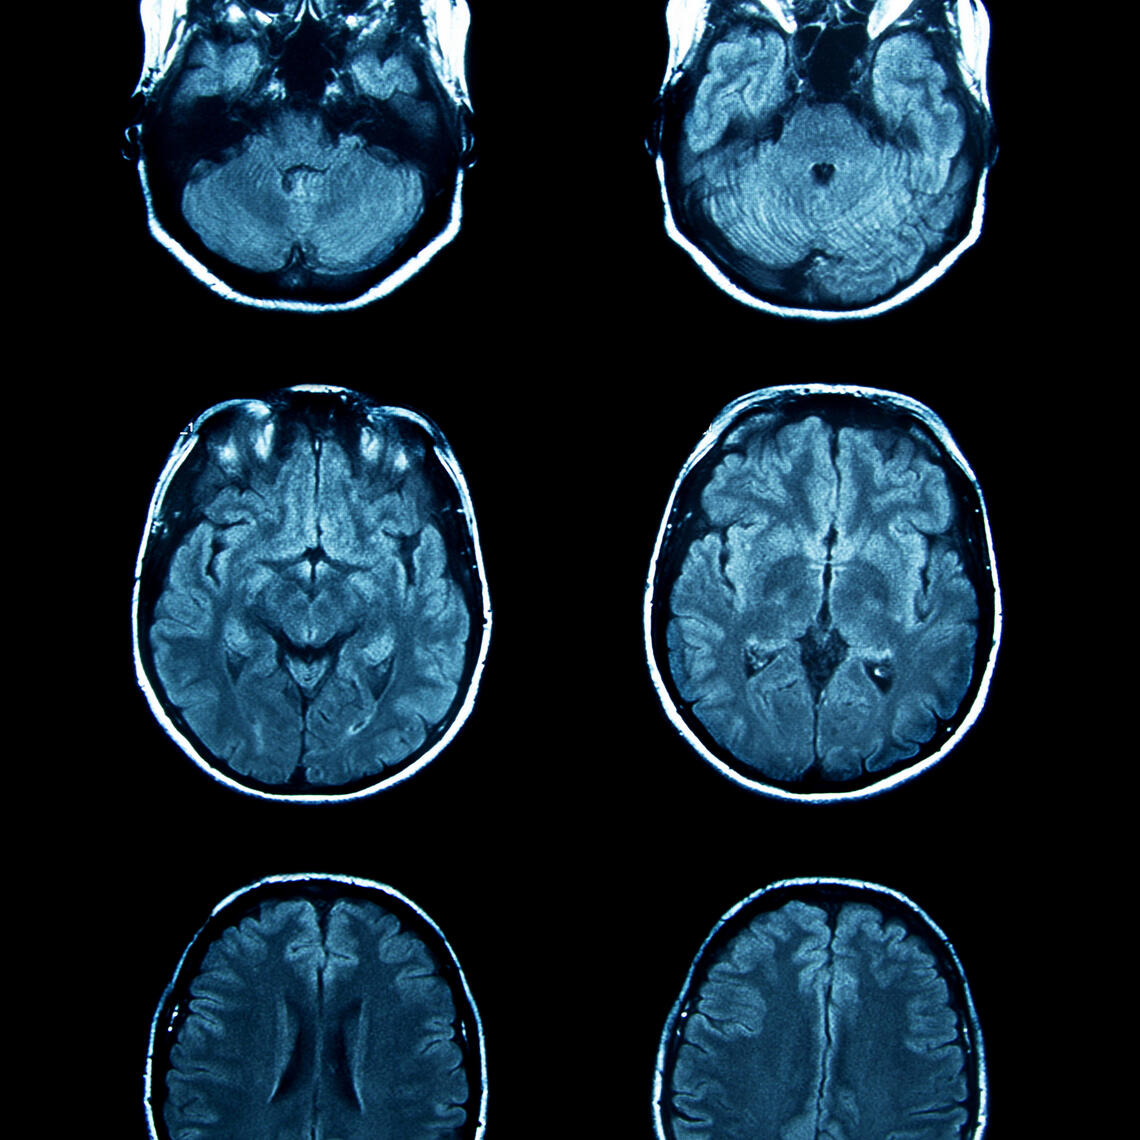

Robotics: NeuroArm brings neurosurgery to new heights. A team of Calgary surgeons has successfully used a robot to remove a tumour from a young woman's brain. The surgical robotic system, called NeuroArm, helped surgeons remove the tumour from 21-year-old Paige Nickason. The machine is being dubbed the world's first MRI-compatible robot able to perform both surgery and biopsies in a less invasive way for patients. Read more.

Precision health: Magnetic resonance-guided focused ultrasound (MRgFUS) is a revolutionary new technology that allows surgeons to access the brain without cutting the skin or drilling into the skull. Elias Pharaon is 85 years old and can sign his name for the first time in five years thanks to a new way to do brain surgery. Read more.